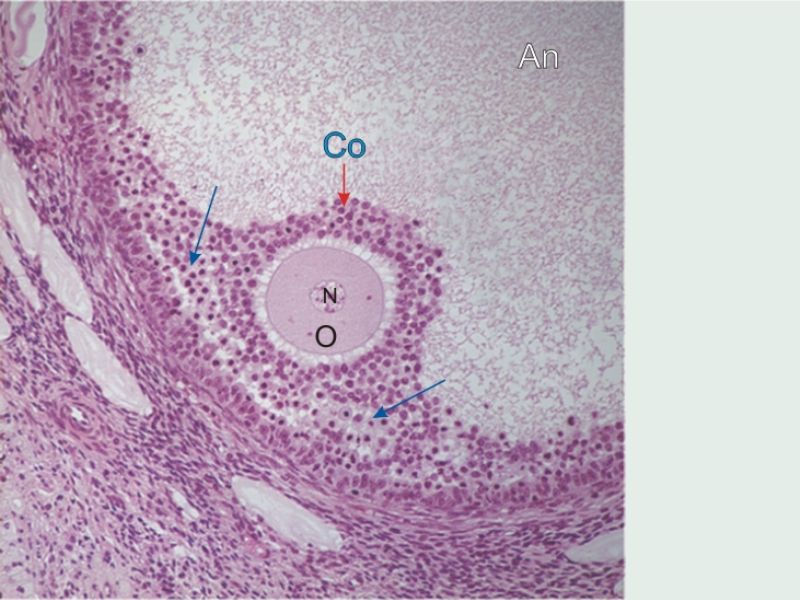

Ovaries

Slide 24

Section of the ovary

1. Outer covering. 1'. Attached border. 2. Central stroma. 3. Peripheral stroma. 4. Bloodvessels. 5. Vesicular follicles in their earliest stage. 6, 7, 8. More advanced follicles. 9. An almost mature follicle. 9'. Follicle from which the ovum has escaped. 10. Corpus luteum.

Ovary

- Capsule covered by modification of peritoneum

- Called germinal epithelium

- Simple squamous/cuboidal

- Subdivided

- Not clearly defined

- Cortex - contains ovarian follicles

- Medulla - vascular

Follicular maturation

- Primordial follicle

- Growing follicle

- Primary follicle

- Secondary follicle

- Mature follicle (Graafian)

Components of a follicle

- Theca

- externa

- interna

- basal lamina

- Granulosa cells

- Antrum

- Cumulus oophorus >> Corona radiata

- Oocyte